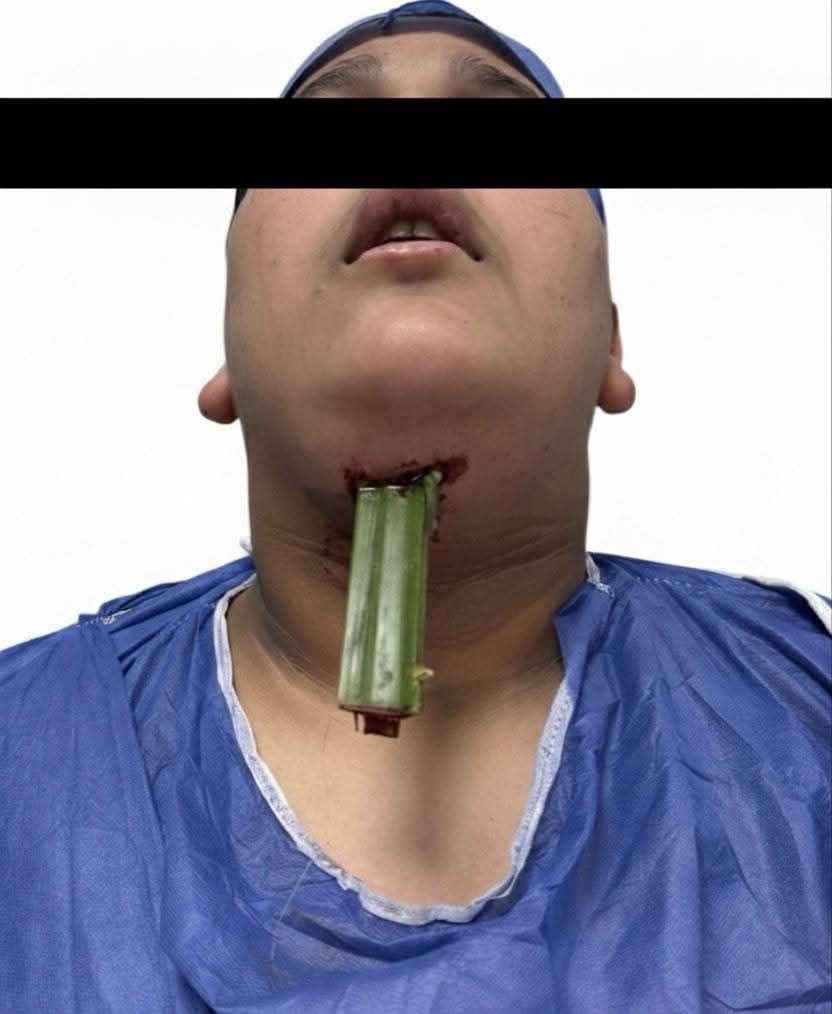

نجح الفريق الطبي بقسم جراحة الوجه والفكين والجمجمة بمستشفى العجوزة التخصصي في تحقيق إنجاز طبي جديد، حيث تم التعامل مع حالة نادرة ومعقدة لطفل يبلغ من العمر 15 عامًا تعرض لسقوط أدى إلى دخول جسم غريب بطول 20 سم اخترق الرقبة واللسان وسقف الحلق وتوقف أمام قاع العين مباشرة ممتدًا حتى الجمجمة.

وقد تسبب هذا الاختراق في تهتك شديد بالأنسجة والأوردة والشرايين، كما شكل تحديًا كبيرًا لفريق التخدير نظرًا لتمركز الجسم الغريب أمام مجرى التنفس وصعوبة التعامل معه أثناء التخدير.

ورغم دقة الحالة وخطورتها، نجح فريق جراحة الوجه والفكين بالمستشفى في استخراج الجسم الغريب بدقة عالية وتقطيب الجروح والقطوع الجراحية، دون الحاجة إلى إجراء شق حنجري كما كان مقررًا، كما خرج المريض من غرفة العمليات إلى غرفته مباشرة بحالة مستقرة دون الحاجة إلى الدخول للرعاية المركزة أو استخدام أجهزة التنفس الصناعي.